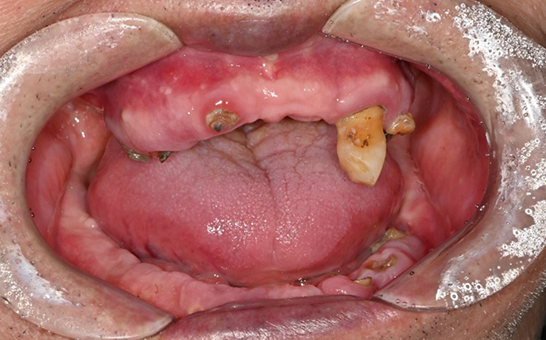

CASE 01 김** / 60대

전악임플란트

치료 시작 전 촬영 2024.01.24 | 치료 완료 후 촬영 2024.12.26

1 예후불량 치아 발치

2 발치 후 즉시 임플란트 식립 및 뼈이식

3 고정성 보철물로 수복 후 일상 회복